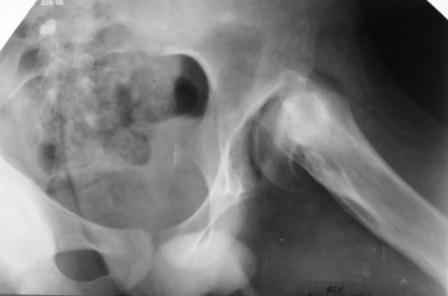

[Ortho] дисплазия тазобедренного сустава

Имя     : PICT0229.JPG